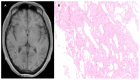

Vascular malformations are frequent in the head and neck region, affecting the nervous system. The wide range of therapeutic approaches demand the correct anatomical, morphological, and functional characterization of these lesions supported by imaging. Using a systematic search protocol in PubMed, Google Scholar, Ebsco, Redalyc, and SciELO, the authors extracted clinical studies, review articles, book chapters, and case reports that provided information about vascular cerebral malformations, in accordance with Preferred Reporting Items for Systematic Reviews and Meta-Analyses (PRISMA) guidelines. A total of 385,614 articles were grouped; using the inclusion and exclusion criteria, three of the authors independently selected 51 articles about five vascular cerebral malformations: venous malformation, brain capillary telangiectasia, brain cavernous angiomas, arteriovenous malformation, and leptomeningeal angiomatosis as part of Sturge-Weber syndrome. We described the next topics-"definition", "etiology", "pathophysiology", and "treatment"-with a focus on the relationship with the imaging approach. We concluded that the correct anatomical, morphological, and functional characterization of cerebral vascular malformations by means of various imaging studies is highly relevant in determining the therapeutic approach, and that new lines of therapeutic approaches continue to depend on the imaging evaluation of these lesions.